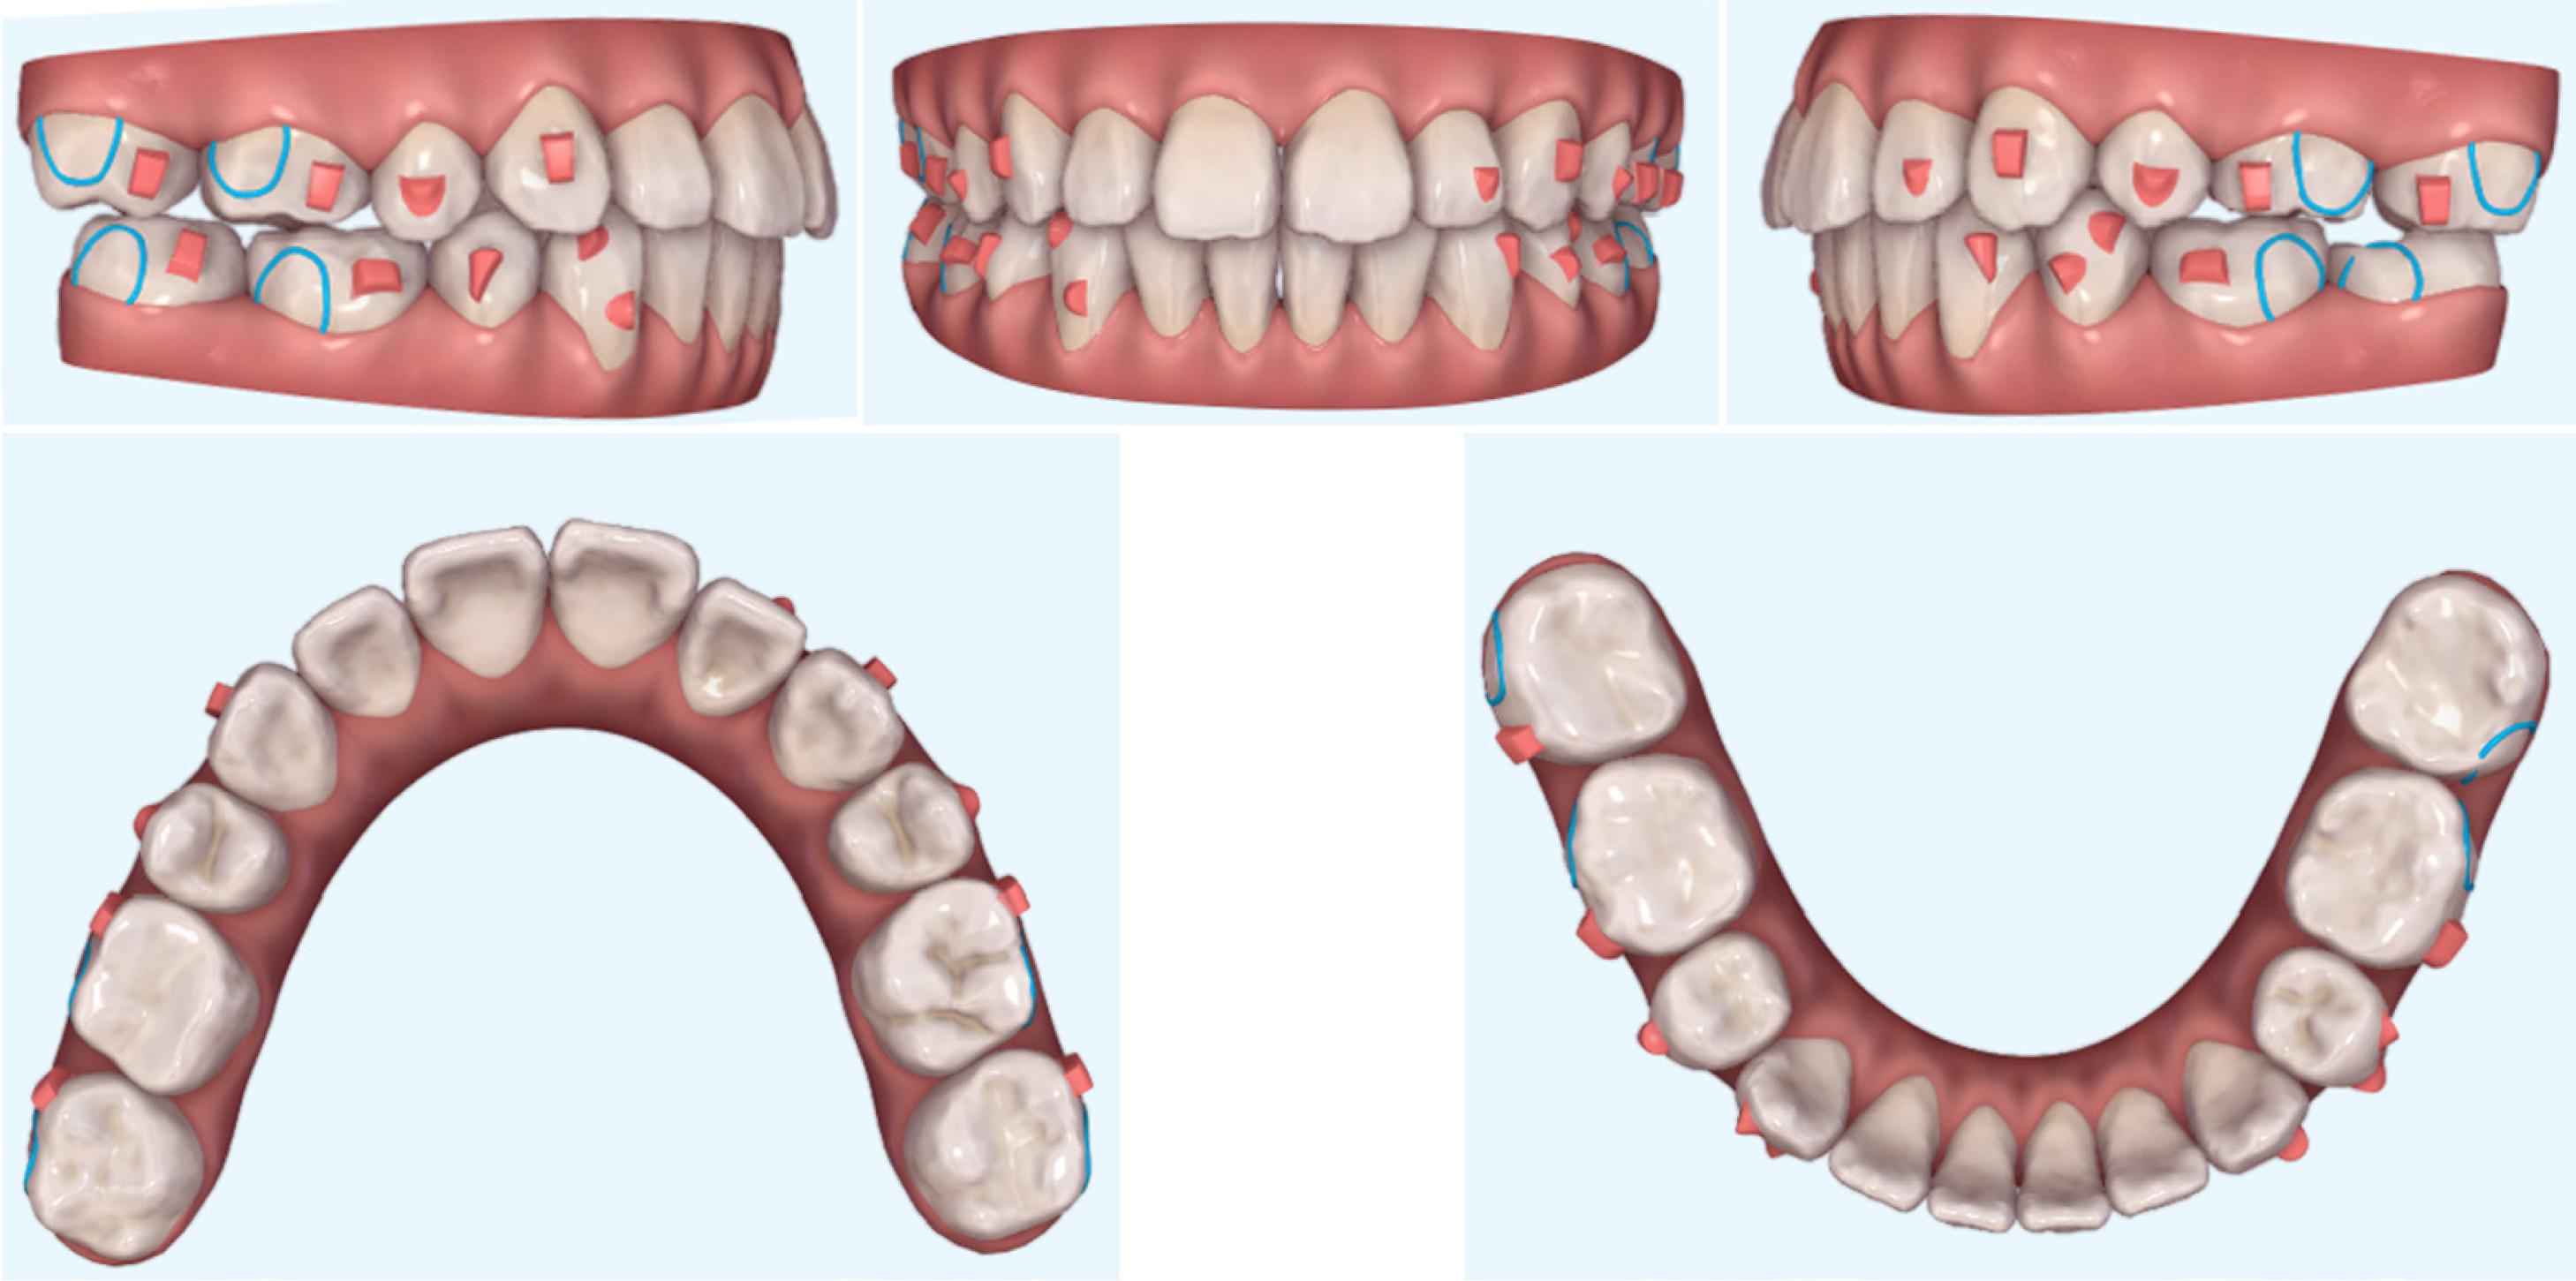

The treatment commened by extracting the four premolars. The goals of the initial phase were to align and level the dental arches, close the extraction spaces, and close the open bite. In the upper arch, 14, 24, 13, and 23 were retracted, leaving a space at the mesial area of 13 and 23. The anterior teeth were aligned, and 8° of lingual root torque was added prior to en-masse retraction. The teeth 16 and 26 were moved first, allowing further mesialisation of 17 and 27, until 16 and 26 contacted 14 and 24, respectively. Optimised retraction attachments were applied to the upper canines, as well as optimised anchorage attachments and vertical rectangular attachments on the upper posterior teeth. An extrusion attachment was designed and placed on the upper right incisor through an automated process. In the lower arch, the treatment plan was to retract 33 and 43, thereby leaving space mesial to 33 and 43 (which improved aligner grip), adding 10° of lingual root torque before en-masse retraction of the incisors. The G628 solution for optimised retraction attachments was used on the canines and optimised anchorage attachments on the lower posterior teeth. The patient wore bilateral Class III, 3.5-ounce elastics, full time throughout the treatment phase. It was planned to intrude the upper posterior teeth by approximately 2 mm, extrude the upper anterior teeth by approximately 1.5 mm, and finally achieve an overbite of roughly 3 mm. In addition, it was planned to expand the maxillary arch in order to co-ordinate the arch forms. Palatal crown torque of 17 was necessary to achieve a normal buccal overjet of the right posterior teeth. The pre-treatment ClinCheck treatment plan is presented in Figure 5.

Pre-treatment ClinCheck treatment plan (Align Technology, Santa Clara, CA, USA).

The final sets of aligners underwent improvements to correct the anterior overbite and mild posterior open bite that developed during treatment. During refinement, 15 upper and 10 lower aligners were worn for 9 months and were changed every 14–30 days. The patient’s overbite decreased by attaching power ridges and the subsequent intrusion of the anterior teeth. The posterior open bite was corrected by placing button cutouts in the maxillary and mandibular aligners for attaching vertical elastics. The ClinCheck treatment plan for the refinement stage is presented in Figure 6. While additional improvements may have been possible, the patient was satisfied with the results at the end of this stage; therefore, the treatment was terminated. At the outset, it was considered that the difference in the alignment and position of the anterior teeth before and after treatment was large, and so Hawley retainers combined with bonded lingual wires for retention were provided. However, the patient was unable to adapt to these retainers because of her occupation and socialising, so vacuum-formed and transparent full-arch wraparound retainers were supplied to maintain the treatment results.

Refinement stage: ClinCheck treatment plan (Align Technology, Santa Clara, CA, USA).